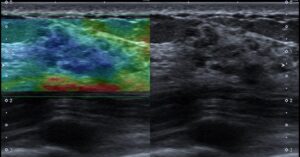

エラストグラフィグラフィは?と思いやってみると

歪みの低下もある…!

施行後すぐに医師に画像を確認してもらうと、

要精査となり他施設へ紹介し、病理組織の結果はDCISでした。